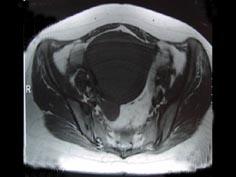

问题 女性,36岁,腹痛,自觉摸到包块,行B超检查提示盆腔内巨大包块,进一步行MRI检查,如图所示,考虑为 ( )

选项 A、卵巢囊肿 B、膀胱憩室 C、子宫腺肌瘤 D、子宫癌 E、子宫肌瘤

答案 C